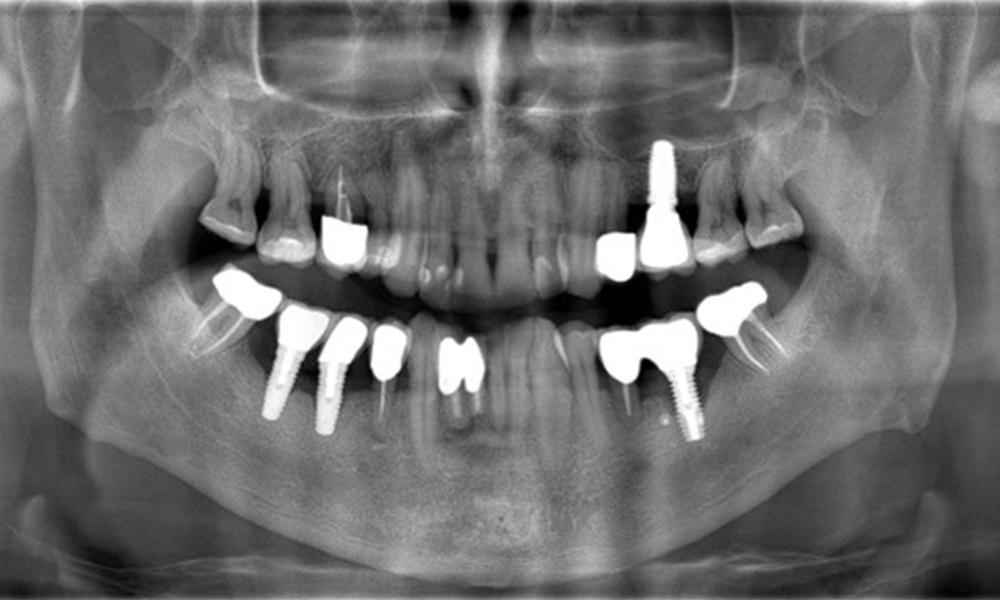

The X-ray images show the progression of bone loss. OPG from 29.06.2020 (left) and OPG from 26.02.2024 (right).

OPG: 26/02/2024 Dental X-ray: 18/01/2024